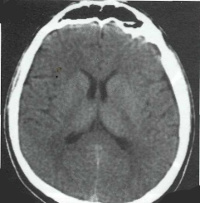

Субдуральная гигрома - это возникшее в результате ЧМТ отграниченное скопление цереброспинальной жидкости в субдуральном пространстве, вызывающее сдавление головного мозга.

Субдуральная гигрома